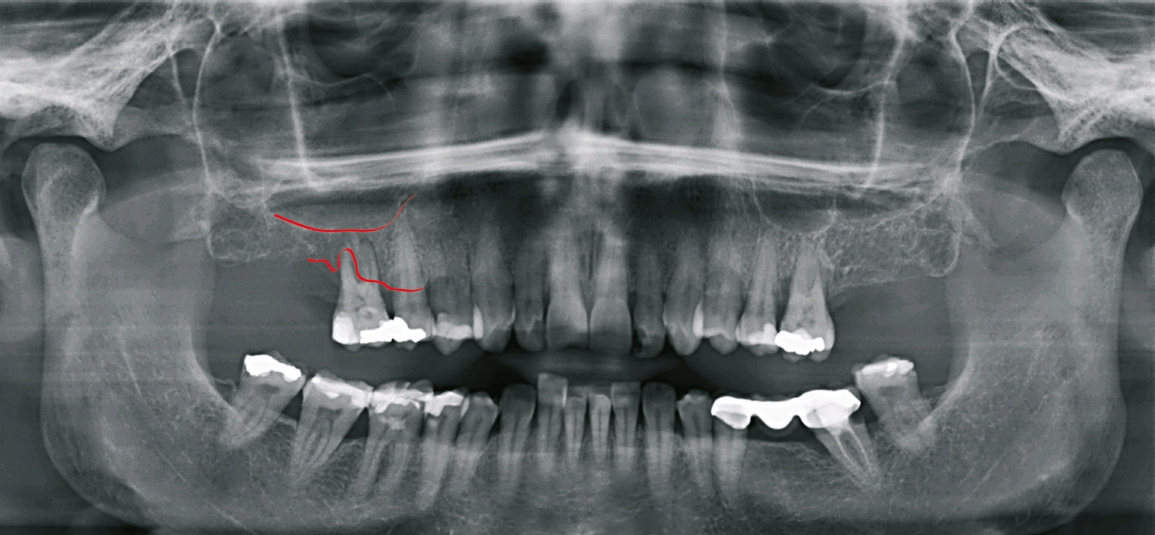

Patient 1: männlich, 50 Jahre alt, Anamnese: unauffällig; Diagnose: Schaltlücke. Knochenersatzmaterial: Geistlich Bio- Oss® (Geistlich Biomaterials) (Abb. 5 bis 10).